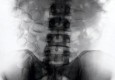

Fidelis Ozouli izdvojen je iz grupe putnika na aerodromu u Manchesteru, kada su službenici postali sumnjičavi u vezi njegovog izgleda. Naredili su rentgen i ostali zapanjeni onim što su vidjeli. Količina kokaina dovoljna da napuni dva konzumna pakiranja šećera nalazila se u njegovom…